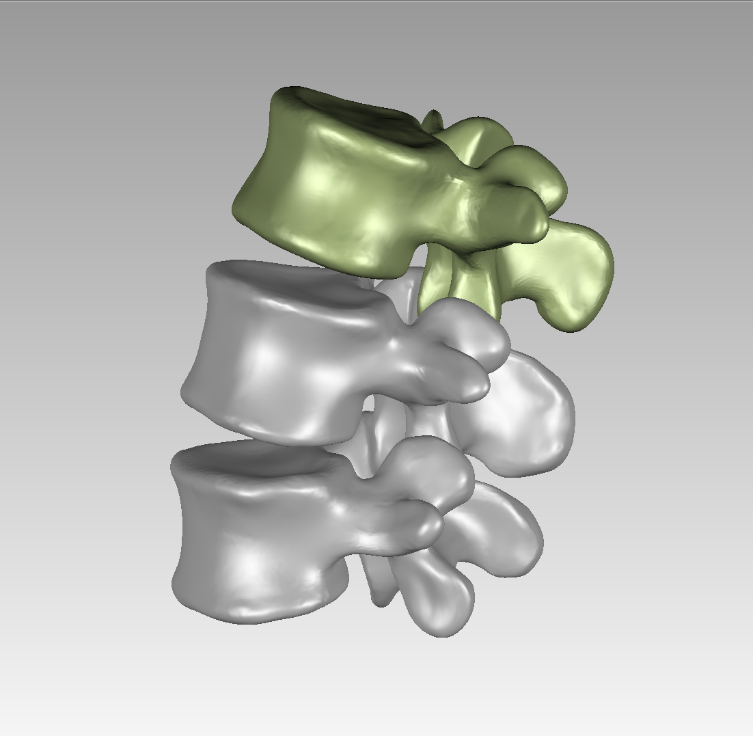

选取一名27岁青年男性志愿者在我院行腰椎螺旋CT扫描�����,扫描平面为���:第十二胸椎椎体至尾椎末端���,扫描厚度为0.625mm���,得到二维断层CT图像489张��,以DICOM格式进行储存���,导入计算机服务器�����。使用Mimics 19.0图像生成和编辑处理软件��,直接读取 DICOM格式的CT扫描数据进行三维重建���,见图 10����。根据软件中不同的灰度值来区分不同的组织����,用 Mimics 软件的阈值分割及区域增长功能画出腰椎(L3-5)����,不同的锥体用不同的颜色区分���,最后用图像填充功能填补图像中的空洞���,接着进行不同部位的三维重建��,得到仅包含骨性结构(L3-5)的模型��。将Mimics 软件得到的模型以STL格式模型文件导入Geomagic wrap2017软件中���,抹去模型钉状物和多余特征��,然后对模型进行优化光滑处理�����,将L3-5光滑处理后的每个锥体进行复制���,再将光滑后的模型在精确曲面中进行网格划分����,并进行构建曲面片及修理曲面片����,最后合成三维实体模型����,见图11�����。此时将复制的每个椎体模型外层向部件内部偏移2mm�����,内部充当松质骨��,外部的则定义为皮质骨����,椎弓根后部统一由皮质骨组成�����。随后将模型以STEP格式文件导入Solidworks2020软件中生成L3-5的实体模型零件��,并在模型零件中构建椎间盘��、髓核����、上下终板和软骨����,完成的实体模型���,此时的模型为单纯的正常腰椎三维几何模型���,各结构并未赋予材料属性与网格划分����,见图12�����。将模型导入ANSYS软件中���,随后对模型中皮质骨���、松质骨���、软骨����、终板���、纤维环���、髓核赋予相应的材料属性赋值���,尽可能地还原各组织材料的生理状况�����,提高模型的可靠性���。定义关节突关节面为 Frictional����,摩擦系数设为0.1��。在connections中建立spring模块���,模拟前纵韧带����、后纵韧带���、黄韧带��、棘间韧带���、棘后韧带���、横突间韧带及关节囊韧带��,各韧带对应刚度赋值��。建立完成后�����,对模型进行mesh操作构建网格���,见图13����。

图 10 Mimics 图 11 Geomagic